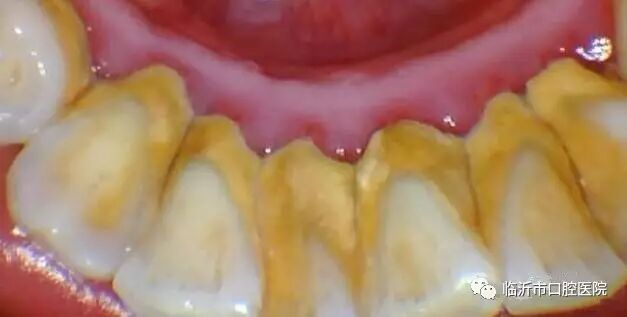

牙结石又称牙石,通常存在于唾液腺开口处的牙齿表面。如下颚前牙的舌侧表面,上颚后牙的颊侧表面和牙齿的颈部,以及口腔黏膜运动不到的牙齿表面等处。牙结石最开始是乳白色的软垢,通过逐渐钙化变硬。它是由75%的磷酸钙,15%~25%的水、有机物、磷酸锰、矿酸钙及微量的钾、钠、铁所构成。牙结石通常呈现出黄色、棕色、或黑色等,有的与自然牙颜色相近,有的则明显可见差异

牙结石一旦钙化,就等同于在口腔中落地生根,建立了生存的基地。但这位大恶魔并不会就此止步,而是继续开枝散叶、呼朋引伴,随着时间的推移越积越多、越级越厚,并逐渐向牙颈部位发展,形成更为隐形也更为可怕的“龈下结石”。

牙结石从牙冠逐渐向下蔓延,牙结石每进步一些,牙槽骨就萎缩一些,久而久之,牙齿就逐渐松动,牙结石便见缝插针,逐渐蔓延到牙根部位。对口腔而言,结石是一种异物,它的存在本身就会不断刺激牙周组织并压迫牙龈,影响口腔局部血液循环,造成牙周组织病菌感染,引起牙龈发炎萎缩,形成牙周袋。当牙周袋形成后,食物残渣、牙菌斑和结石等更易堆积,进一步的破坏更深的牙周膜,如此不断的恶性循环的结果,终至牙周支持组织全部破坏殆尽,牙龈出血、牙周疾病等随之而来。总而言之,如不能及时清除,被牙结石缠上的牙齿最终逃脱不了溃烂脱落的命运。